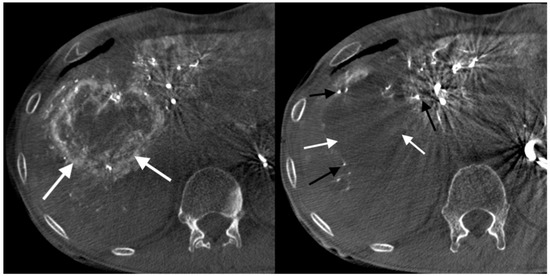

- Grade 4 stasis. Embolizate contrast in segmental vessels (Figure 4).